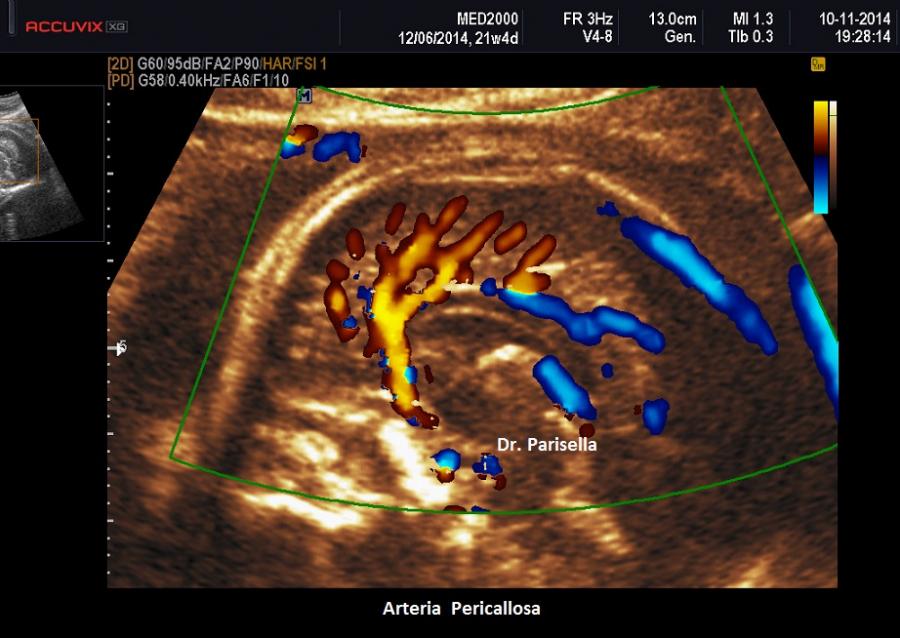

Le anomalie del corpo calloso, (agenesia, disgenesia/ipoplasia) possono essere di difficile diagnosi, specie quando non si riesce ad ottenere un buon piano sagittale. Può essere di aiuto visualizzare con l'ausilio del color Doppler il decorso dell'arteria pericallosa che normalmente decorre lungo la faccia superiore del corpo calloso. In caso di agenesia l'arteria pericallosa non è evidenziabile; in caso di disgenesia/ipoplasia il decorso dell'arteria pericallosa si interrompe a livello della porzione mancante.

• assenza dell'arteria pericallosa;